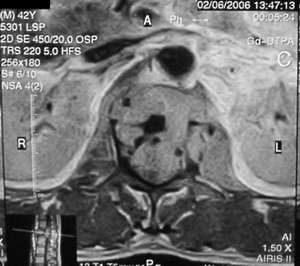

男,42岁。半年前体检发现右侧肺门肿大,mri示右侧肺门淋巴结肿大。腰背部疼痛伴右腿麻木1月入院。腹部b超示肝、胆、胰腺、脾、肾、前列腺及膀胱未见异常。afp、cea、ca199均正常。

增强图像显示不清,好像有肺门及纵隔与腋下淋巴结肿大,右侧胸腔积液,腰1椎体骨质破坏,椎旁软组织肿块形成,其后硬脊膜囊明显受压。考虑淋巴瘤可能。其他待排。

腰椎骨质破坏,但未侵及椎间盘,椎前软组织肿胀,考虑腰椎转移瘤可能